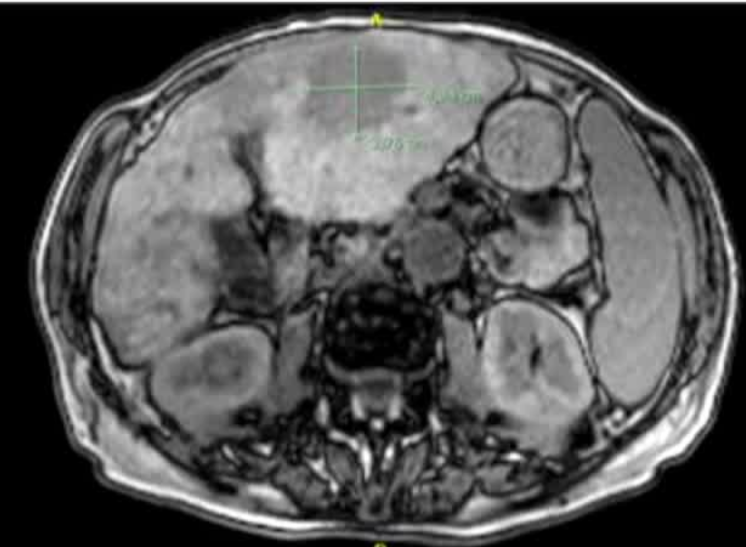

本文是一篇关于评估肝内胆管癌(Intrahepatic Cholangiocarcinoma, ICC)患者在接受超声引导下的经皮微波消融(Microwave Ablation, MWA)治疗后预后的研究论文。研究旨在确定白蛋白-胆红素(Albumin-Bilirubin, ALBI)分级是否可以用来预测这些患者的治疗结果。该研究是一项回顾性研究,涵盖了2011年4月至2018年3月期间接受MWA治疗的52名初治患者及其74个肿瘤病变。

研究对象:52名未接受过治疗的ICC患者,共74个肿瘤病变,符合米兰标准。

-

随访时间:中位随访时间为21.2个月(范围3.2-78.7个月)。

总体生存率(OS):1年、3年和5年的累积OS率分别为87.4%、51.4%和35.2%。

无复发生存率(RFS):1年、3年和5年的累积RFS率分别为68.9%、56.9%和56.9%。

并发症:主要并发症发生率为3.8%(2/52)。

ALBI 1级患者的1年、3年和5年OS率分别为95.5%、72.4%和72.4%。

ALBI 2级患者的1年、3年和5年OS率分别为62.5%、40.6%和36.3%,两者之间存在显著差异(P = 0.006)。